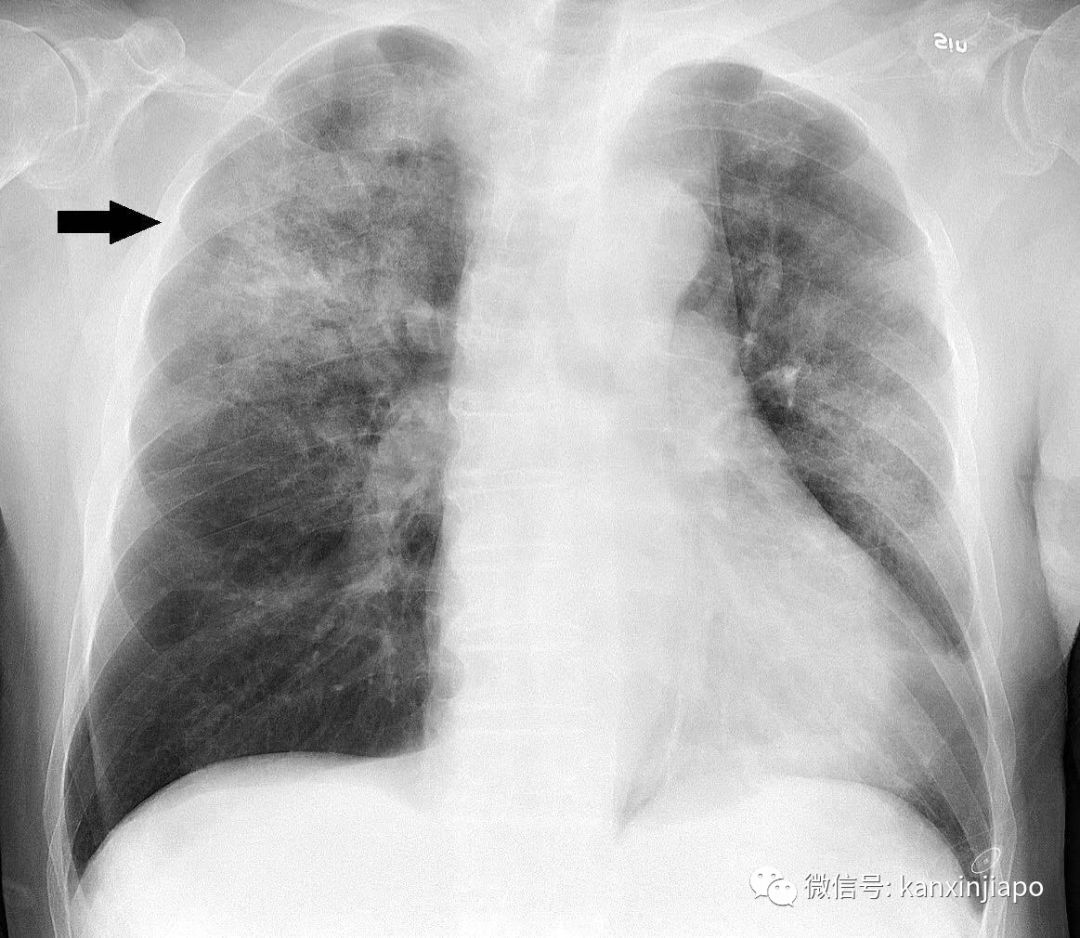

(1月11日),中国湖北省武汉市卫生健康委员会发布最新通报称,武汉肺炎出现首起死亡病例,死者为一位61岁男性。

通报介绍了死者的具体情况:他常年在武汉市华南海鲜市场采购货物,因呼吸衰竭、重症肺炎入院,并同时患有腹部肿瘤及慢性肝病。截至今天,除了仍有7人患有重症外,其余患者病情稳定。与这些患者密切接触的共计739人,均已接受医学观察,没有发现相关病例。武汉市卫生委员会还另外作出强调,自2020年1月3日以来未发现新发病例。目前,未发现医务人员感染,未发现明确的人传人证据。